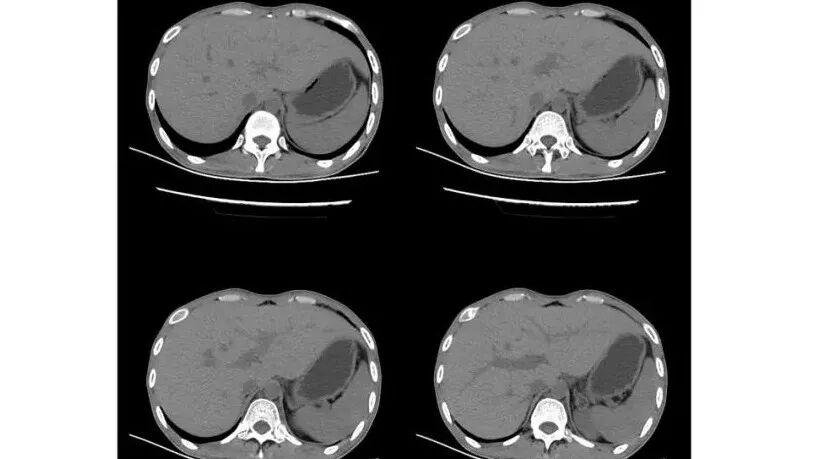

以下为2021-7-15日上腹部CT

影像与临床:1.青年男性,HlV阳性,颜面部皮疹(未提供皮疹图像)、发热(高热),实验室CRP、PCT高,T-Spot阴性。2.右肺下叶空洞结节,壁厚不均,边界清楚,其内线状影,未见液平及钙化,未见卫星灶,纵隔淋巴结增大,双侧腋窝见增大淋巴结。心腔内低密度提示贫血可能。肝脾影增大,未见结节影及块影。腹膜后见多发增大淋巴结。

综合分析:本例肺部影像学改变并不具有特征性,空洞性病灶须与多种疾病鉴别,但年轻HIV阳性患者,高热,皮疹,肝脾增大,纵隔、腋窝、腹膜后见多发增大淋巴结等都强烈提示马尔尼菲篮状菌感染的可能性。